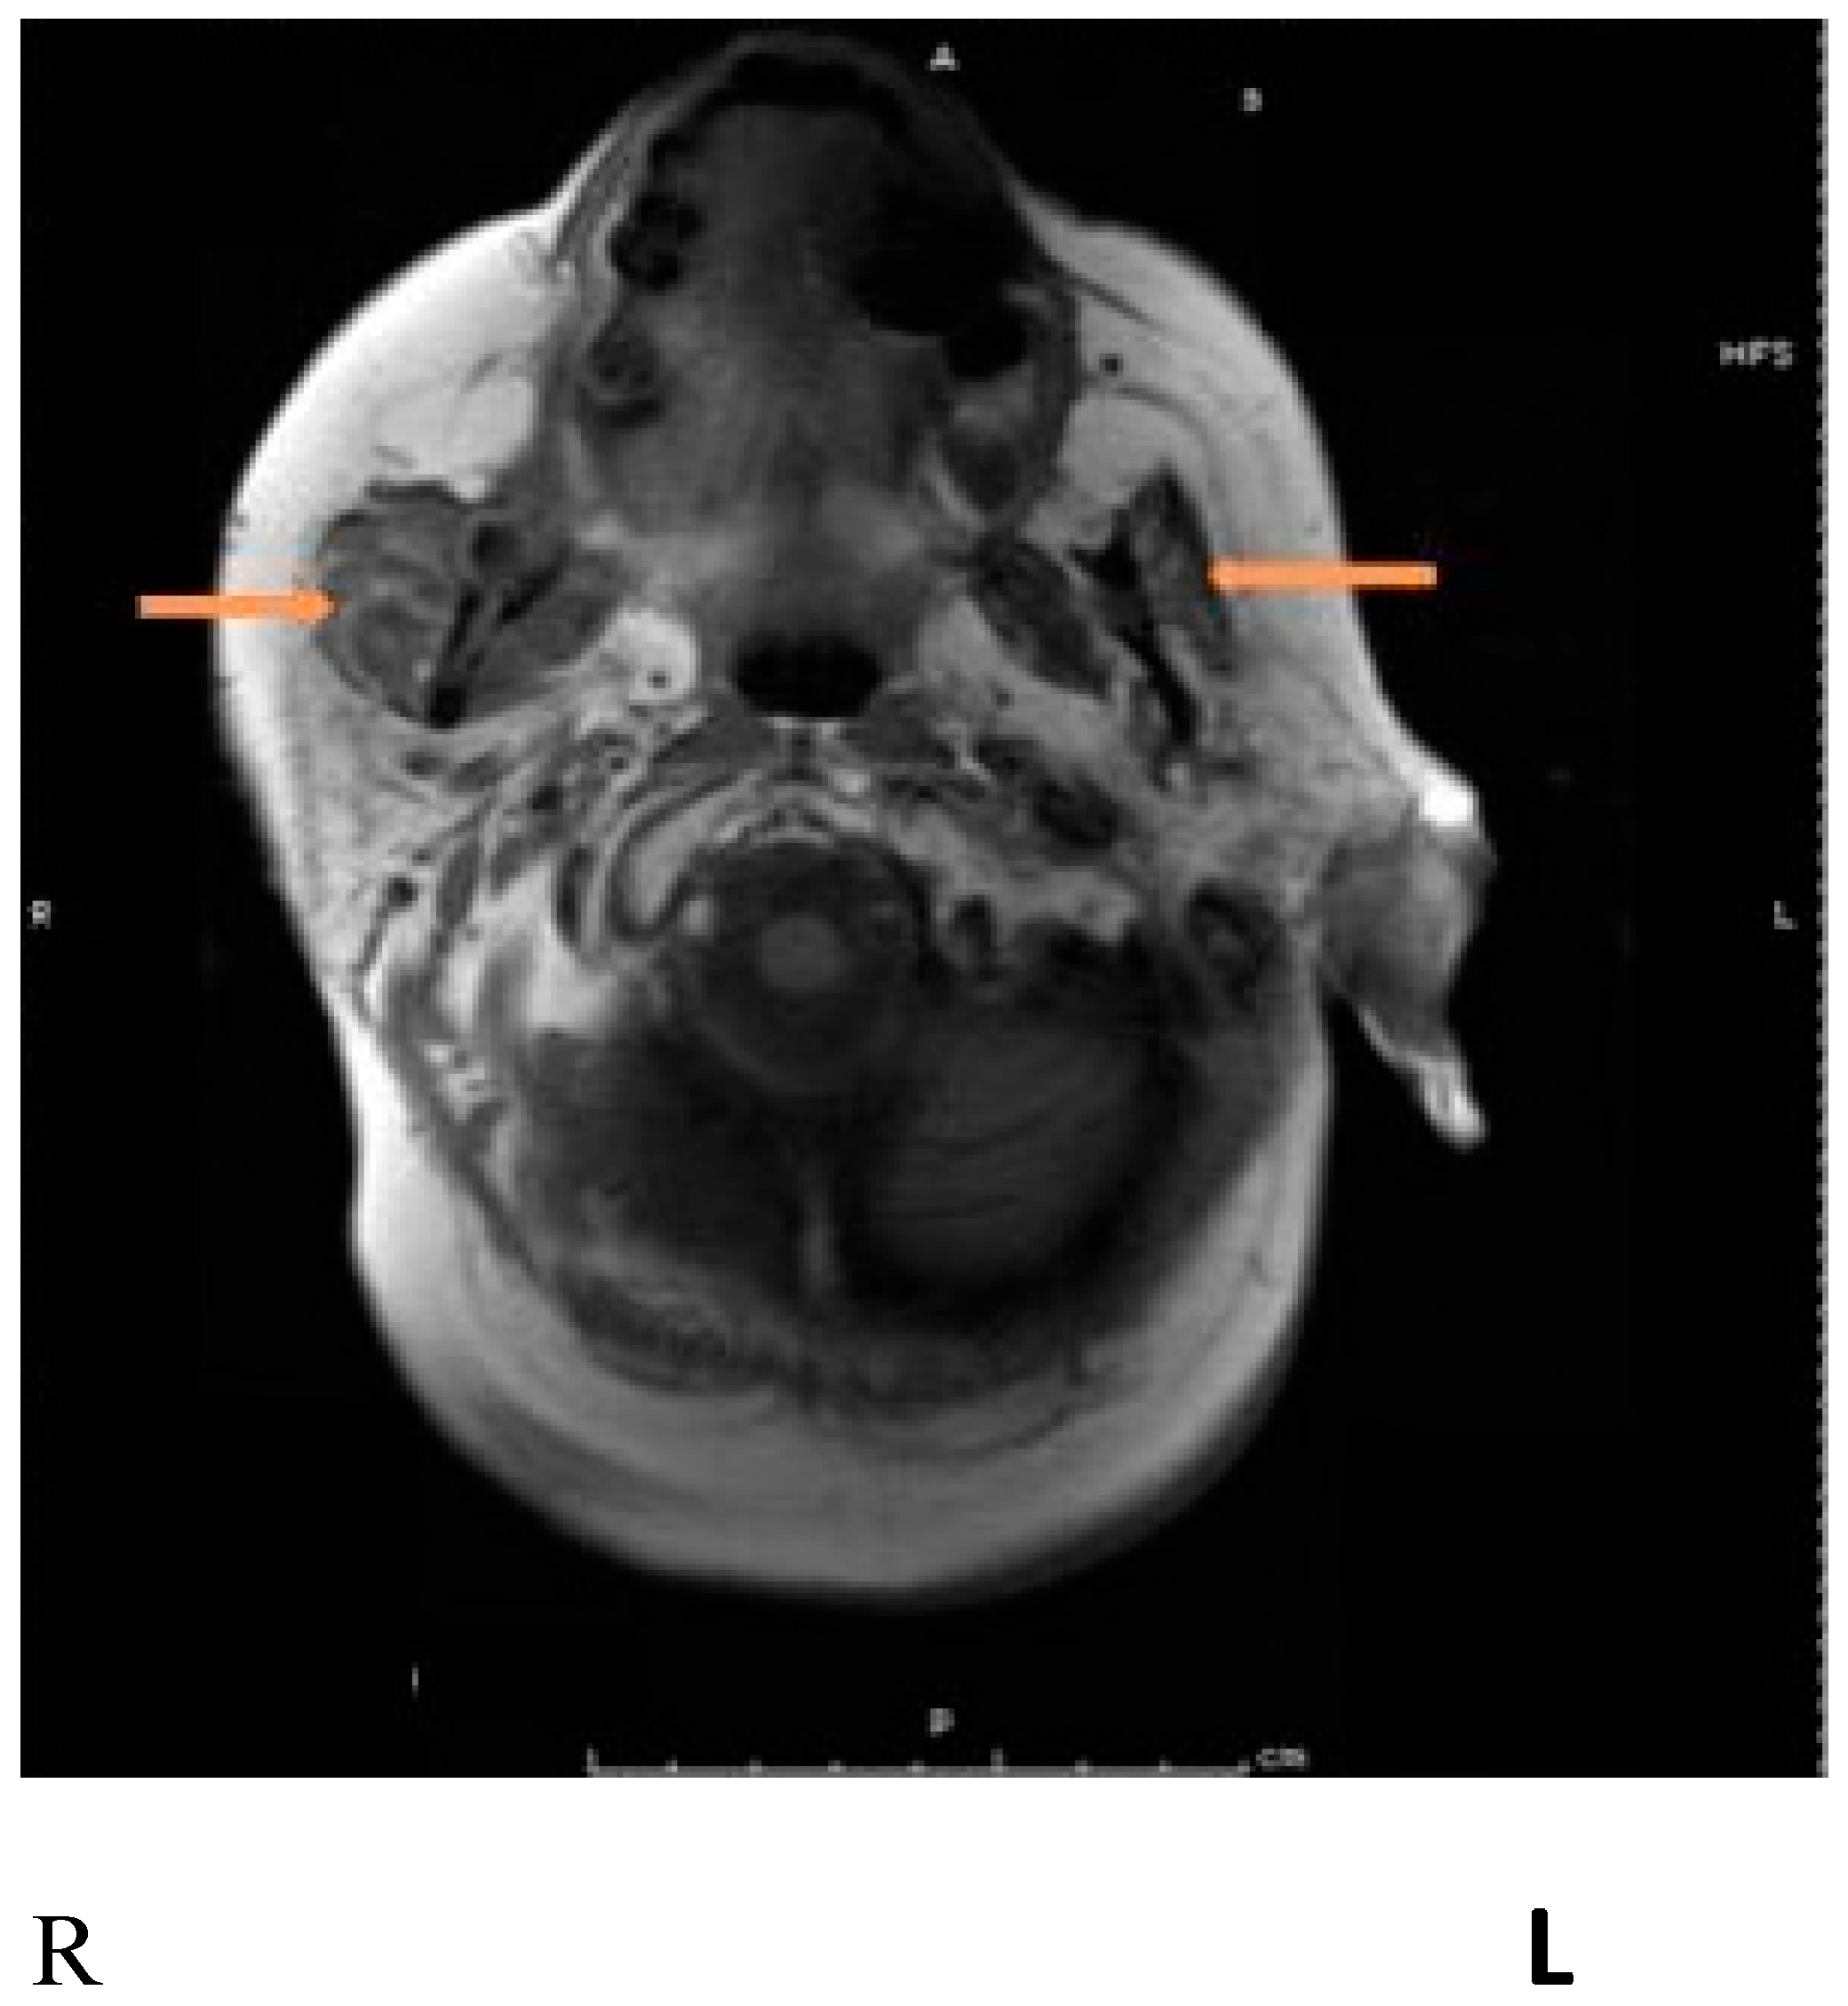

8. Parotidectomy and Parotid Radiation

9. First Bite Syndrome